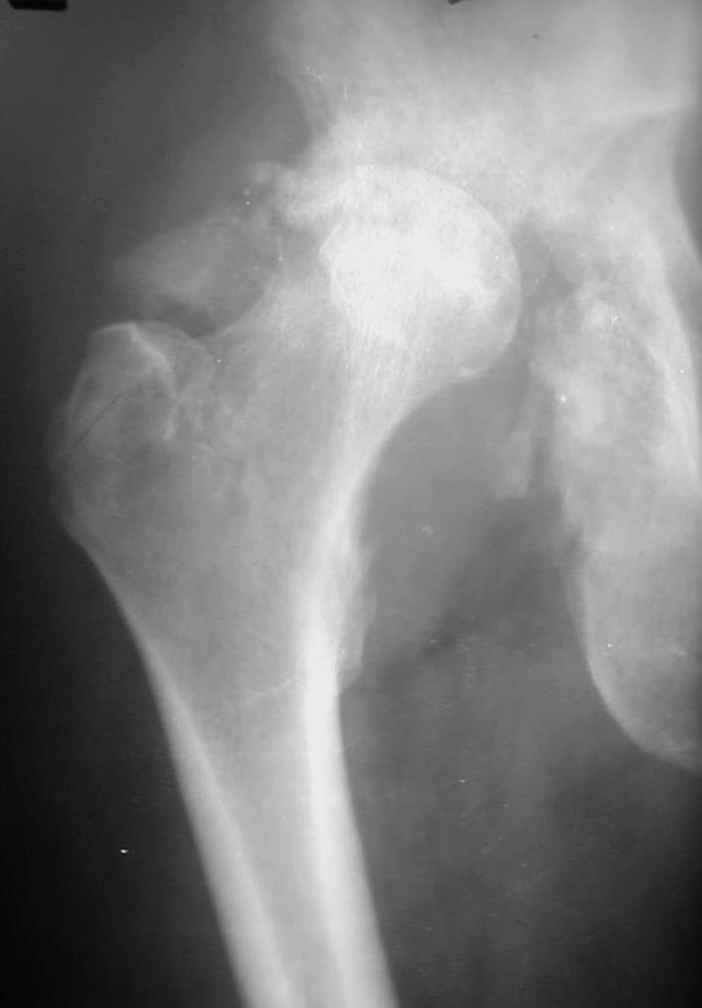

1 год